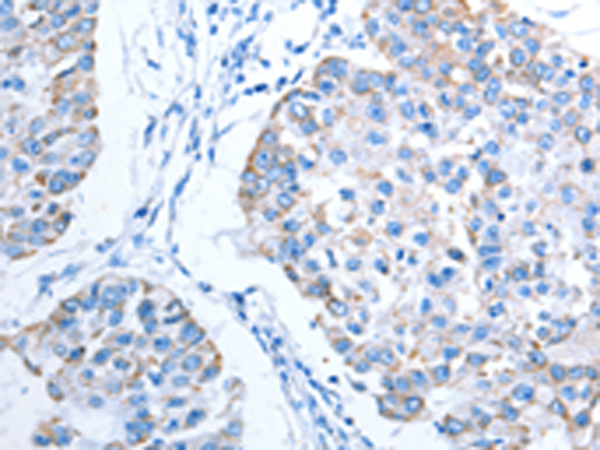

分类: 科研抗体货号: P07824别名: PI; A1A; AAT; PI1; A1AT; PRO2275; alpha1AT应用: IHC反应种属: Human

分类: 科研抗体货号: P07822别名: ORM; AGP1; AGP-A应用: WB,IHC反应种属: Human

分类: 科研抗体货号: P07819别名: CDGIi; NET38; hALPG2应用: IHC反应种属: Human, Mouse

分类: 科研抗体货号: P07808别名: ALAS; MIG4; ALAS3; ALASH应用: IHC反应种属: Human, Mouse, Rat